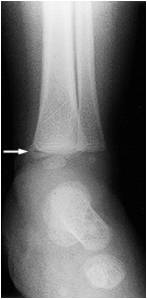

Fractura en Asa de cubo

Niño de 7 semanas Rayos X